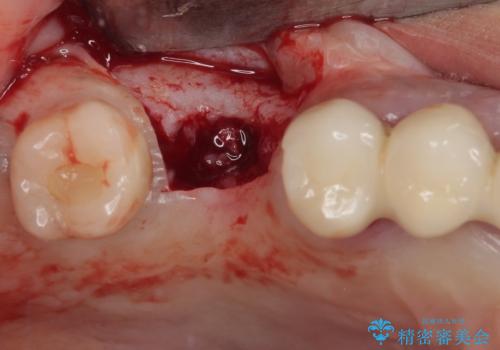

- インプラントが脱落してしまったとのことで来院された患者様です。

歯肉は綺麗に治癒しており、インプラント埋入に十分な骨があったため、速やかにインプラント埋入を行うこととしました。

インプラント埋入の状態が良ければ即日で仮歯を装着し、十分な生着が確認され次第、オールセラミッククラウンにて補綴治療を行うこととしました。

インプラントの初期固定も埋入後の生着もスムーズであったので、埋入から3ヶ月で無事に治療を終えることができました。